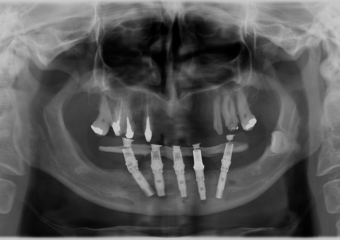

Raio-x Implantes Superiores em Julho de 2015 - Clínica Cliniface

Raio-x Implantes Superiores em Julho de 2015